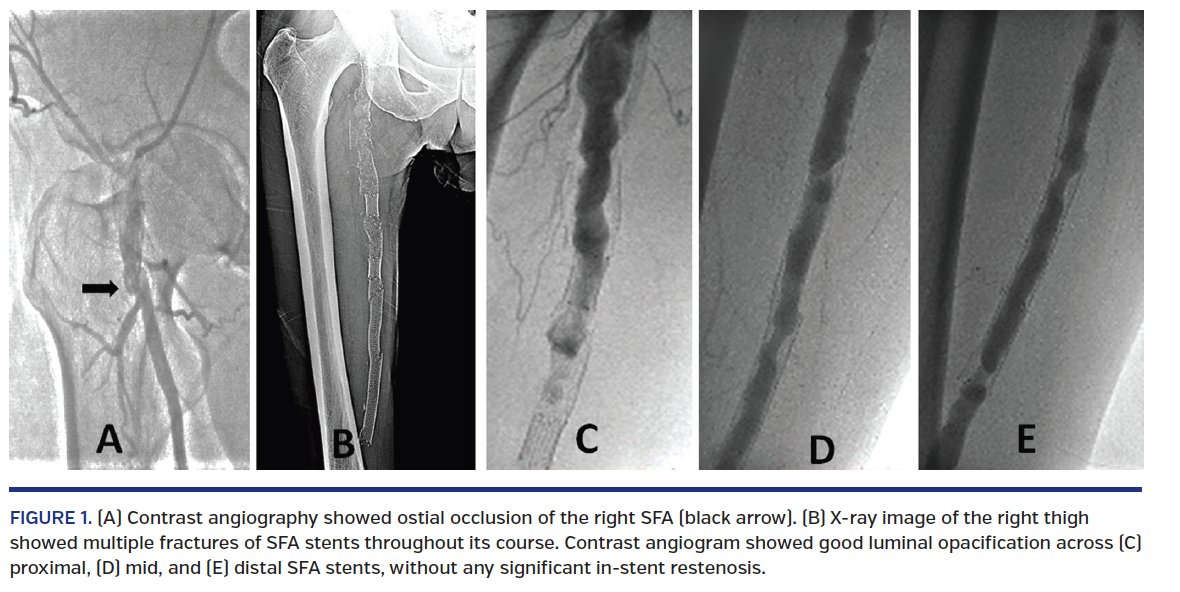

A 58-year-old, chronic smoker, hypertensive man presented with right lower-limb claudication (Fontaine stage IIb) of 1-year duration. Right lower-limb ankle-brachial index was 0.6. Doppler ultrasound and computed tomography confirmed proximal long-segment occlusion of the right superficial femoral artery (SFA). Contrast angiography confirmed ostial occlusion of the right SFA (Figure 1A). The patient had undergone successful percutaneous transluminal angioplasty and stenting of the SFA with 3 overlapping, self-expanding nitinol Smart stents (Cordis) in sizes 8 x 120 mm, 8 x 60 mm, and 8 x 150 mm extending from ostial to distal SFA (Video 1). During a recent admission for non-Q wave myocardial infarction after 5 years of asymptomatic follow-up, fluoroscopy revealed multiple type-III stent fractures of the right SFA stents (Figure 1B; Video 2). Right lower-limb ankle-brachial index was 0.95.Contrast angiogram confirmed good flow across the SFA with insignificant in-stent restenosis (Figures 1C-1E). He was continued on optimal medical treatment for coronary and peripheral arterial disease.

Certain factors like ostial disease, chronic total occlusion, and long, multiple stents are the main causes of multiple stent fractures, as were present in this case. Such stent fractures are usually associated with significant in-stent restenosis; however, this patient had a patent lumen despite multiple fractures.